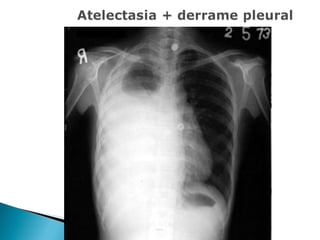

   Colapso alveolar:

. Diminuição dos espaços intercostais.

. Insuflação do lado contralateral.

. Desvio do mediastino ipsilateral.

   Derrame pleural:

. Opacificação homogênea do ângulo

costofrênico.

. Contorno diafragmático obscurecido.

. Desvio ipsilateral do mediastino ou contralateral

(quantidade).

   Pequeno: menor que 500 ml

   Médio: entre 500 e 1000 ml

   Grande: acima de 1000 ml